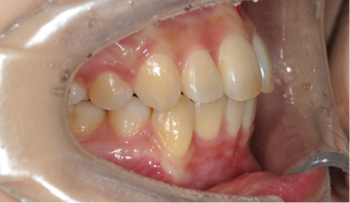

​​​​​​​Case 01. 덧니 & 치열 불규칙

덧니가 있거나 치열이 불규칙한 경우, 심미적으로도 보기에 좋지 않지만, 기능적으로도 본연의 역할을 상실하게 됩니다.

이 경우 교정 치료 방법은 크게 치아를 빼고 하는 방법과 치아를 빼지 않고 교정하는 방법으로 나뉩니다.

교정 치료 Before & After

• 덧니 & 치열 불규칙 교정 치료 후

After